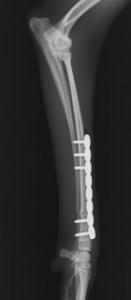

手術前

手術後

ロッキングプレートで整復しました。